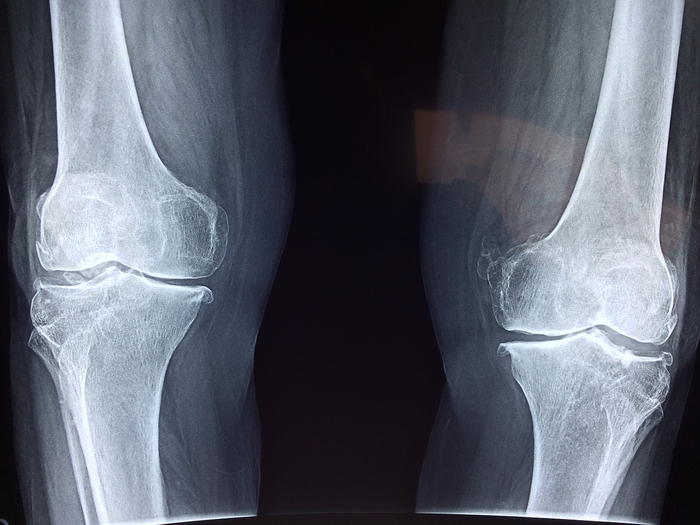

우리 몸에는 수많은 관절이 있습니다. 손가락부터 발가락까지 다양한 관절이 있는데, 이 관절이 주로 움직임을 담당합니다. 손가락이 관절 없이 구부릴 수 없듯이 모든 관절은 동일한 기능을 가지고 있습니다. 그러나 이러한 관절이 질병이나 부상으로 인해 손상되어 이를 치료하려고 하면 관절이 제대로 기능하지 못할 수 있습니다. 위 사진은 대퇴골 골절을 입은 사람의 영상입니다. 원래의 관절을 보존한 채로 수술을 시도했으나 불가능할 경우 인공관절 치환술을 시행합니다. 보상도 있으니 전문가에게 클레임하시고 시작해보시길 추천드려요! 인공 관절 교체

인공관절을 삽입하는 가장 큰 이유는 앞서 언급했듯이 원래의 관절을 사용할 수 없기 때문이다. 고관절에서 가장 빨리 발달하여 가장 많이 사용되고 있으며, 무릎관절, 어깨, 팔, 손가락, 발목관절에도 사용됩니다. 이는 이 관절 기능의 황폐화를 가져오고 있습니다. 또한, 헤드와 접촉부 모두 교체하는 경우를 ‘전체 교체’라고 하고, 헤드만 교체하는 경우를 ‘하프 교체’라고 합니다.